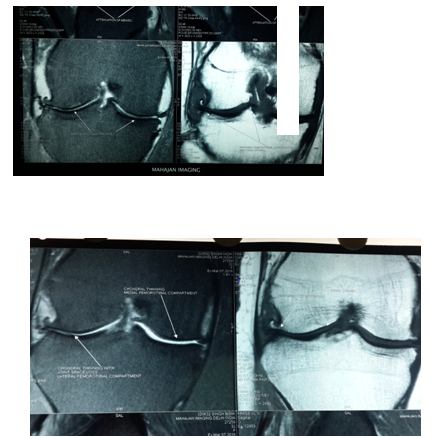

Biochemical test showed decreased level of ESR, CRP and Rheumatoid Titer. X-rays showed less Osteopenia. MRI of knee showed increased thickness in articular cartilage with reduction in synovial thickening and joint effusion. There was visible repair of articular cartilage breach Figures (4-6B).

Figure 6 (A) Pre-stemcell transplantation.

Figure 6 (B) Post stemcell transplantation.